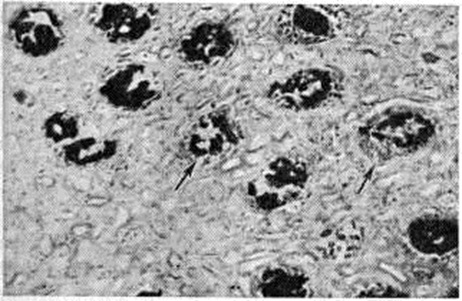

Острый гемоглобинурийный нефроз развивается при отравлении гемолитическими ядами (уксусной кислотой, мышьяковистым водородом, медным купоросом, аминосоединениями, нитросоединениями и другие). При этом морфологический изменения отражают транспорт гемоглобина по системе нефрона; для макроскопической картины типична черно-бурая радиальная исчерченность почечных пирамид, обусловленная наличием пигментных цилиндров (рисунок 3), дающих положительную реакцию Лепене (смотри полный свод знаний: Лепене способ) с бензидином. При отравлении уксусной кислотой гистологически обнаруживается поражение эпителия канальцев проксимальных отделов нефрона, обусловленное реабсорбцией гемоглобина, который выявляется в виде бензидин-положительных гранул в цитоплазме; при электронно-микроскопическом исследовании обнаруживается резорбция гемоглобина в вакуолях клеток с парциальным некрозом апикальных отделов, «перегруженных» пигментом, процесс сопровождается разрывом канальцев дистальных отделов нефрона с выходом в строму содержимого канальца, воспалительной реакцией вокруг него и последующей его облитерацией. Отравление гемолитическими ядами тиоловой группы (мышьяковистый водород, соединения меди и другие) проявляется острым гемоглобинурийным нефрозом в сочетании с коагуляционным некрозом нефроцитов.